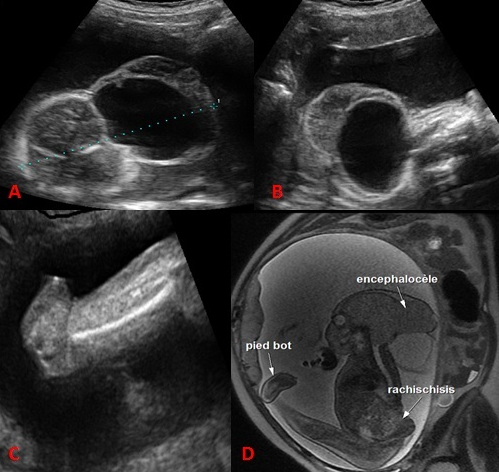

L'iniencéphalie est une malformation rare de la charnière cervico-occipitale. Elle appartient au spectre des anomalies du tube neural. C'est une malformation létale qui touche surtout le sexe féminin. Le diagnostic anténatal par échographie est possible dés 12 à 13 semaines d'aménorrhées (SA). L'iniencéphalie est caractérisée par une extension majeure de la tête, la continuité entre la tête et le tronc et un raccourcissement du rachis et les vertèbres cervicales avec non fermeture de l'arc postérieur. Elle peut être associée à d'autres malformations types une omphalocèle. Il n'y a pas d'indication d'une amniocentèse car il y a absence d'anomalie chromosomique. Le pronostic est sombre puisque elle est létale. Une interruption médicale de grossesse est indiquée une fois le diagnostic est posé. Un conseil génétique sera demandé et une prévention par acide folique sera proposée avant une prochaine grossesse. Nous rapportons l'observation d'une parturiente de 30 ans, grande multipare sans antécédents pathologiques notables. L'échographie de 22SA a révélé une encéphalocéle, une continuité entre la tête et le tronc et un pied bot. L'IRM fœtale a confirmé l'encéphalocéle et le pied bot et a montré une rachischisis. Une interruption médicale de grossesse a été réalisée.